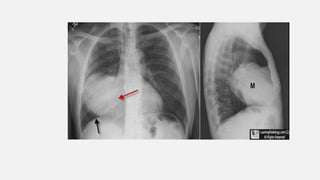

• #7  left upper lobe with fluffy, indistinct margins (red arrow) containing air bronchograms (white arrows). This was found to be a staphylococcal pneumonia.

• #9 n, Right Middle Lobe Mass. On the frontal image, there is a large mass in the right lower lung field. We note it is "silhouetting" the right heart border (red arrow) which is no longer seen as a distinct edge. It is not silhouetting the right hemidiaphragm (black arrow). The mass is therefore (1) touching the right heart border and is anterior and (2) the mass is soft tissue or fluid density. The lateral view shows the mass (M) is in the right middle lobe. It was a large bronchogenic carcinoma. n, Right Middle Lobe Mass. On the frontal image, there is a large mass in the right lower lung field. We note it is "silhouetting" the right heart border (red arrow) which is no longer seen as a distinct edge. It is not silhouetting the right hemidiaphragm (black arrow). The mass is therefore (1) touching the right heart border and is anterior and (2) the mass is soft tissue or fluid density. The lateral view shows the mass (M) is in the right middle lobe. It was a large bronchogenic carcinoma.